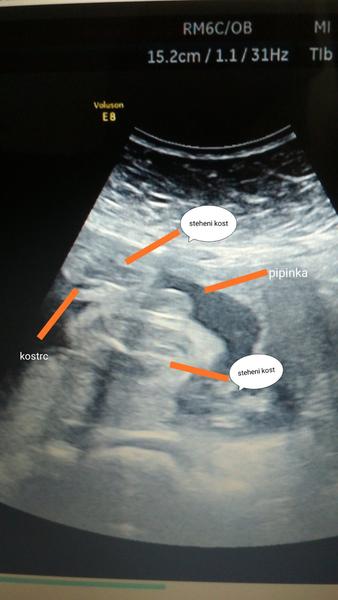

@cysticka no je to foto rozkroku,nevim zda tam jsou steheni kosti a kostrc a na druhe strane pipinka.Uz mam doma 2 kluky a ty to meli jine 😂

Preju ti tu holcicku, ale ta pipka na utz by mela vypadat na kavovy zrno. Tohle mi prijde jako kulicky 🙂

Já si myslím, že kluk.

Já bych teda řekla, ze holčička, pipinku vidim🤔Každopádně držím palecky. Mám doma 2 kočky a utz byl hodně podobný tvému.